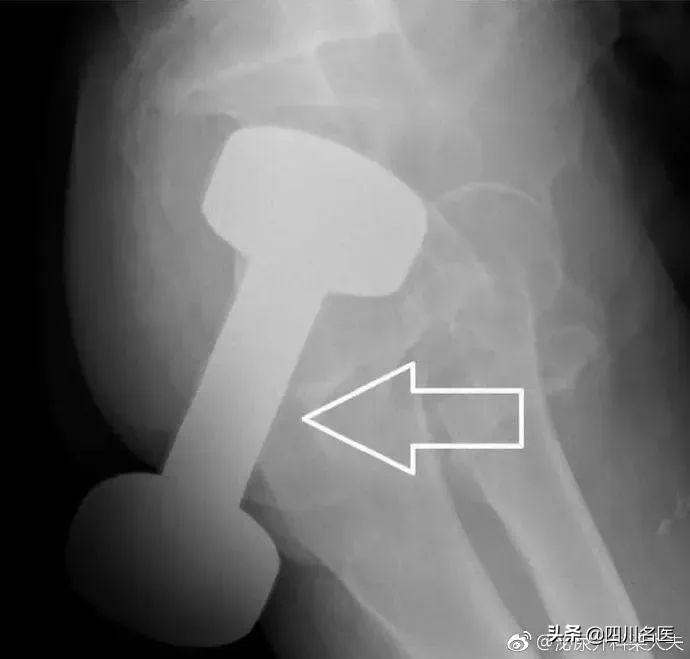

医生会通过一系列检查如直肠指诊、X线来确定体内的异物是什么,在什么位置,这一点非常关键,因为只有搞清楚里面的真实情况,医生才能找到合适的方法把异物取出。